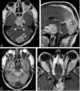

Enhancing sellar lesion